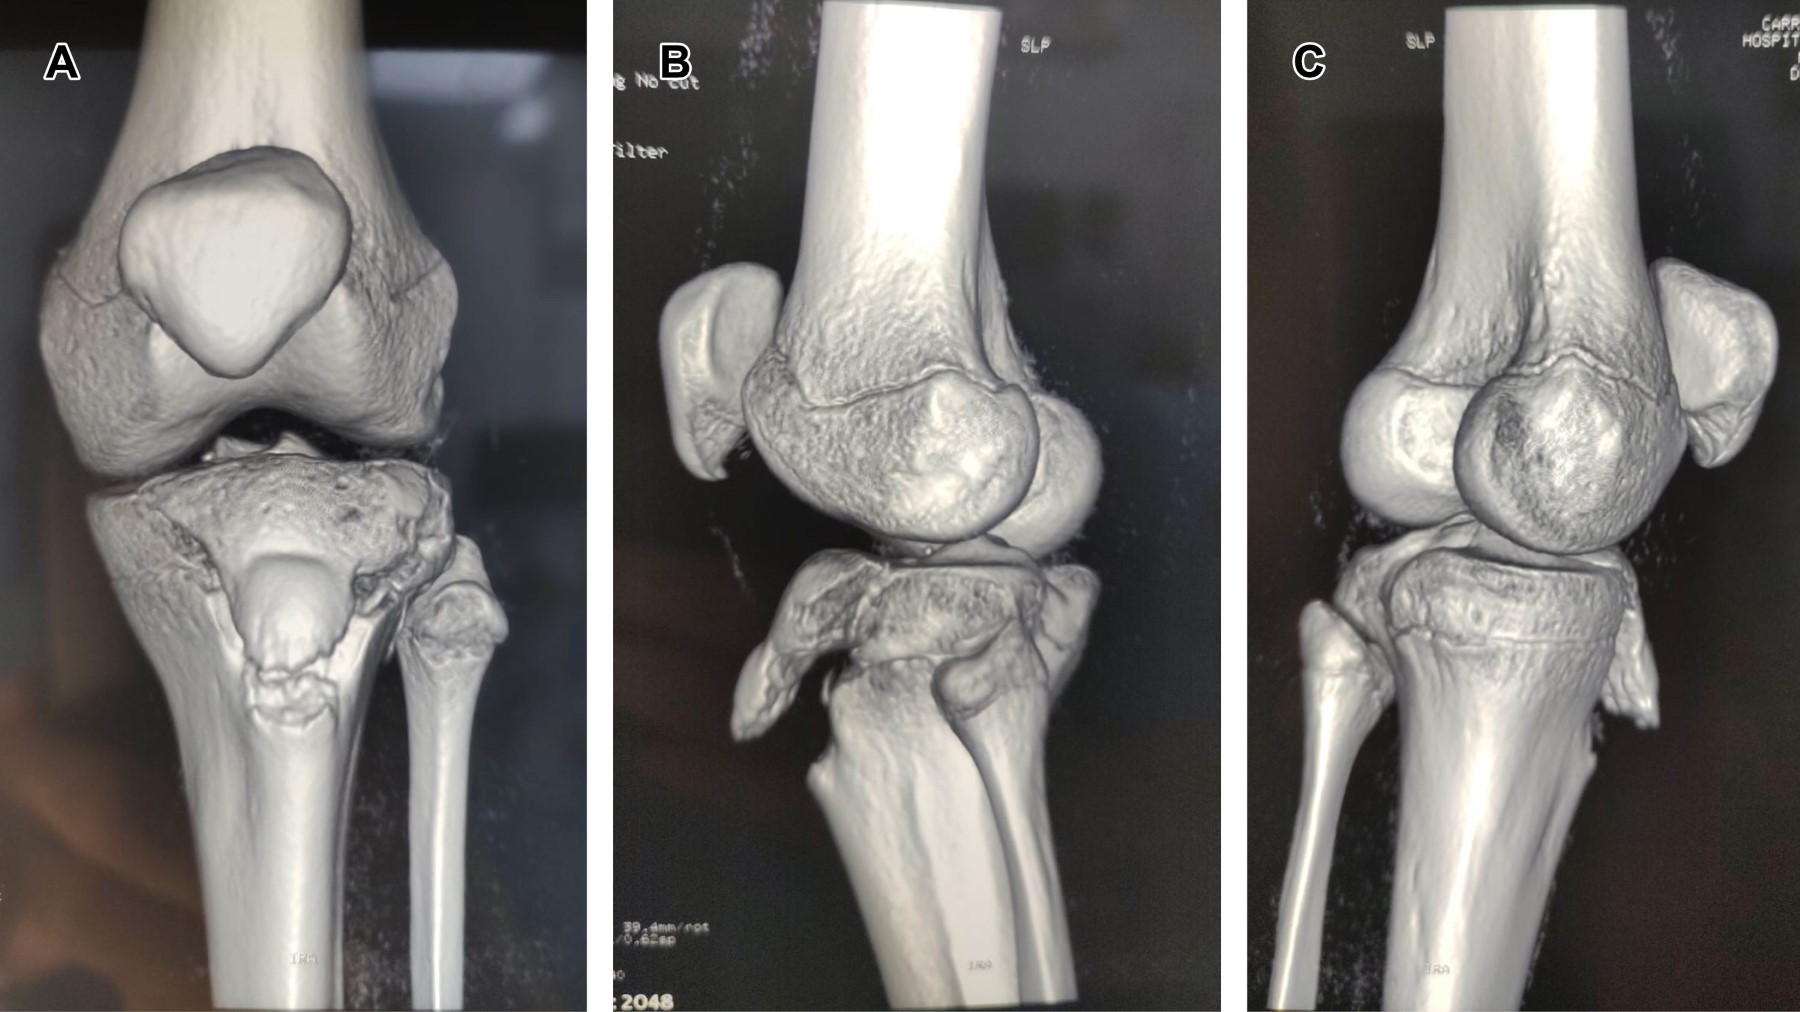

Masculino de 12 años, con estatura de 178 cm, jugador de baloncesto desde los ocho años; quien, realizando ejercicios de marcha en cuclillas, en el momento de cambiar a posición de pie, refiere dolor intenso en rodilla izquierda, acompañado de chasquido, deformidad, e imposibilidad para la función. Es trasladado a urgencias, efectuando diagnóstico de fractura avulsión de tuberosidad anterior de la tibia, corroborando ATT tipo III de Watson y Jones (Figuras 1 y 2), se realizó reducción y osteosíntesis (Figura 3).

El mecanismo de lesión de la ATT es la flexión forzada de la rodilla contra la resistencia del cuádriceps y/o la contracción súbita en extensión de éste, se observa en actividades deportivas que implican salto; se puede asociar a ruptura del tendón patelar, lesión meniscal, de ligamentos cruzados y colaterales. La clasificación de Watson y Jones indica tres tipos: tipo I. Fractura-separación en el centro de osificación secundario del tubérculo; tipo II. Fractura-separación en la unión de los centros de osificación primaria y secundaria entre el tubérculo y la epífisis y; tipo III. Lesión tipo III de Salter y Harris. La línea de separación sigue un trayecto ascendente por el centro de osificación primario de la epífisis tibial proximal, afectando la articulación.2

Figura 2